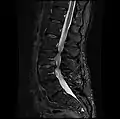

- MRI lumbar spine with degeneration, post-hemilaminectomy L4-5 (sagittal FAST STIR)